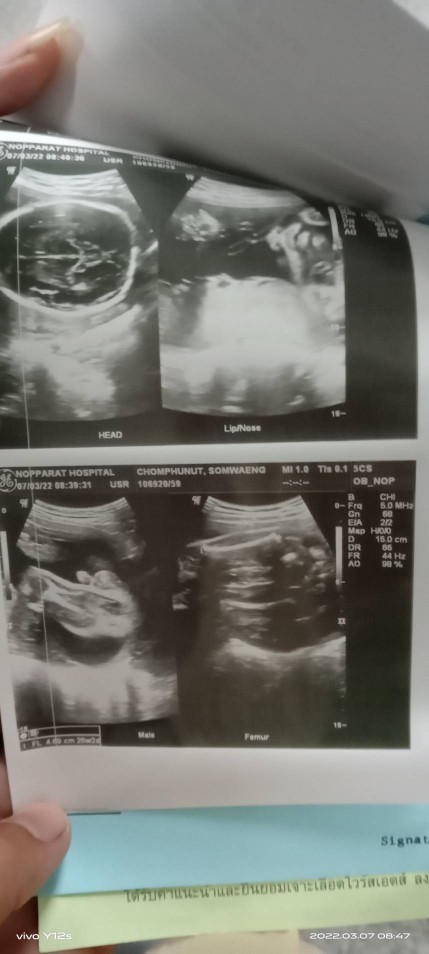

18 w จ้า #เพศชาย #ทีมมิ.ย